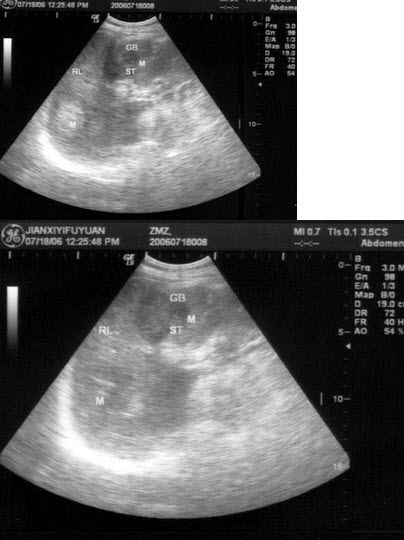

37、单项选择题

女,54岁。反复便秘,腹泻就诊。PE:左中腹可扪及一肿块,质硬,结节状,OB(Ⅱ),结合超声声像图,诊断为()

A.左肾

B.结肠癌

C.肠系膜淋巴结

D.腹膜后肿块

E.肠结核